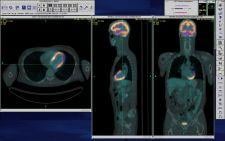

Intuitive Imaging Informatics will feature its PET Fusion at SIIM 2008, designed to provide the ability to combine high-resolution, anatomic images from a CT with functional images produced by PET in an integrated image. The system features user-selectable color maps, real time PET transparency manipulation and automated multi-planar reconstruction (MRP) for orthogonal views. The system also features integrated maximum intensity projection (MIP) for 3D rotational displays.